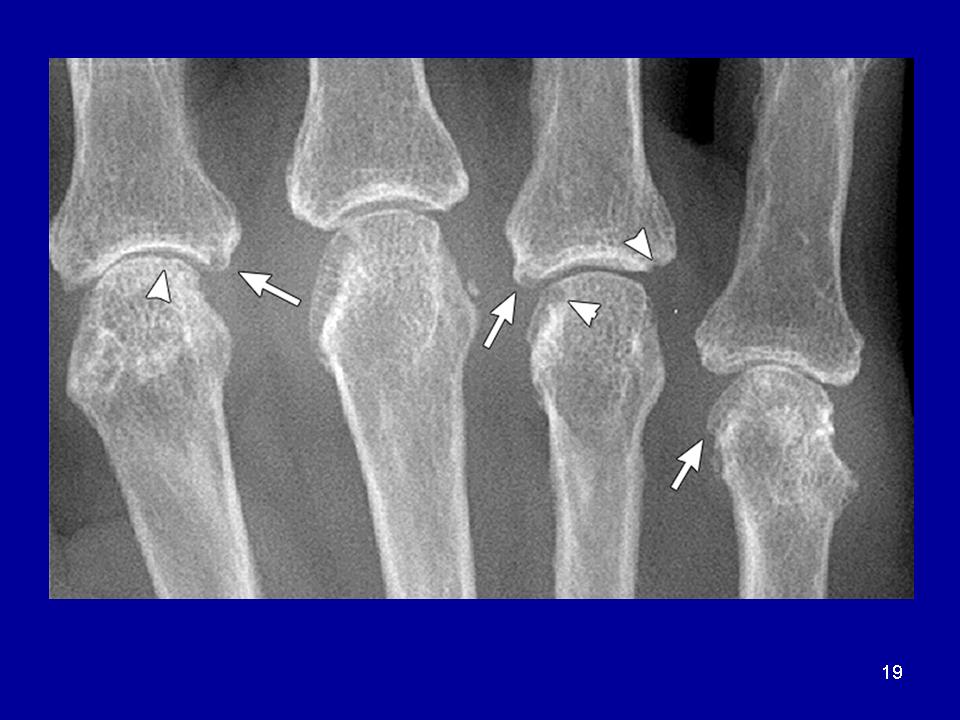

Эрозии суставов. Наличие эрозий суставных поверхностей наиболее характерный для хронического полиартрита рентгенологический симптом, обнаружение которого в типичных для различных ревматических заболеваний суставах подтверждает диагноз. Длительное отсутствие эрозий в мелких суставах кистей требует проведения дифференциального диагноза между ревматическими заболеваниями, для которых не характерно развитие эрозивного артрита. Появление эрозий связано с разрушением субхондральной замыкательной пластины и участка губчатой кости эпифиза сустава. Выделяются 3типа костных эрозий. Наиболее часто в мелких суставах кистей образуются краевые поверхностные эрозии, в тех местах внутрисуставного участка кости, где кость не защищена покрывающим сустав хрящом. Именно эти «оголённые» участки эпифизов костей на краях суставных поверхностей являются первичными местами атаки активно пролиферирующей синовиальной оболочки сустава. Компрессионные эрозии имеют место в том случае, когда происходит провал (коллапс) субхондральной части губчатой кости на фоне околосуставного остеопороза и кистовидной перестройки костной структуры, что приводит к инвагинации суставной поверхности внутрь эпифиза. Важными местами появления данного типа эрозий являются пястно-фаланговые суставы, где коллапс и инвагинация суставных поверхностей проксимальных эпифизов основных фаланг пальцев и смещение пястных головок в эти участки формируют типичные для полиартрита деформации суставов. Компрессионной эрозией также является внедрение ладьевидной кости запястья в дистальный эпифиз лучевой кости. 3-й тип эрозий выявляется в виде поверхностной резорбции замыкательной пластины кости в месте прикреплениясвязки и обычно связан с воспалительными изменениями в смежной связке. Появление такой эрозии по наружному краю шиловидного отростка локтевой кости является важной находкой и представляет собой один из ранних рентгенологических симптомов РА.

Для РА характерны множественные эрозивные поражения суставов. Симметричность поражения является отличительным признаком РА от других ревматических заболеваний. 1-й запястно-пястный сустав поражается при РА редко и его можно отнести к «суставу исключения РА».